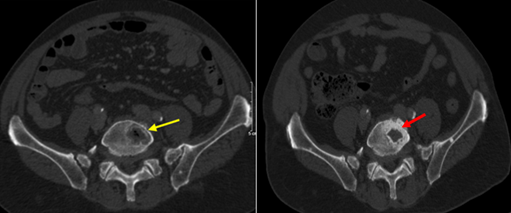

- Chụp CT bụng (tháng 9/2024): Ổ tiêu xương thân đốt sống L4-L5, theo dõi thứ phát

Hình 3: Ổ tiêu xương, phá hủy thân đốt sống L4-L5 (mũi tên vàng)

Hình 9: Hình ảnh CT bụng: hình ảnh tổn thương tiêu xương (mũi tên vàng) giảm bớt sau 6 đợt điều trị, xuất hiện hình ảnh đặc xương tại thân đốt sống (mũi tên đỏ)